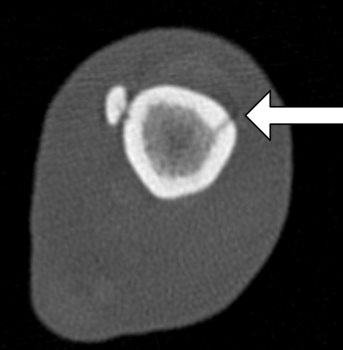

Fractures that are very close to, or even involving joints are more demanding to treat. If the joint is involved then accurate reconstruction is essential to avoid severe osteoarthritis and joint pain. If a fracture or fissure extends very close to a joint it creates difficulties placing implants to achieve sufficient stability for the fracture to heal. In this case a CT was performed to check the exact location of the fissures to help with surgical planning.

After assessing the CT images it was decided that standard plating procedures would carry a significant risk of the fissure propagating, but that a double plating technique using a single locking screw at the lower end of each plate would minimise this risk whilst achieve the minimum requirement for stable fixation. Locking screws have threaded heads that ‘lock’ into the plate. The CT showed that a fissure extended to within 10 mm of the joint surface, but confirmed that it would be safe to place two locking screws at 90 degrees to each other and avoid the fissure and the joint surface.